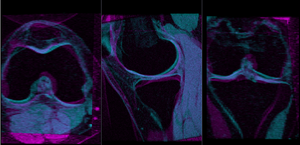

- check the result

- Place "MRI_58" in the background and "MRI_64_Xf3" in the foreground

Registration Results